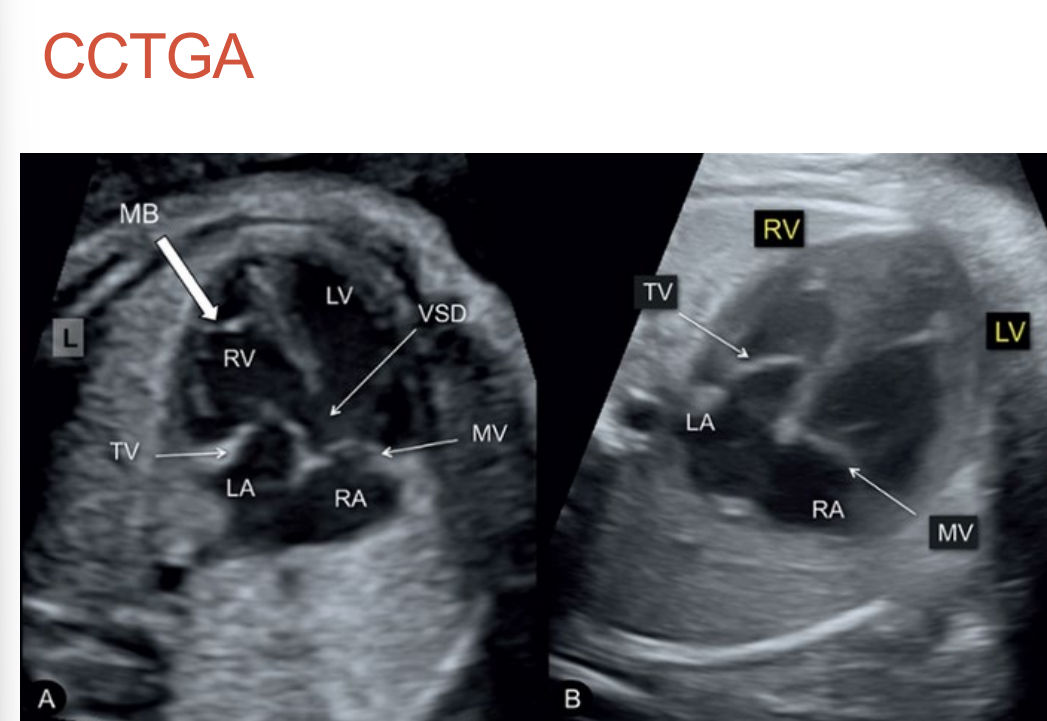

4 chamber will show ventricular inversion • Moderator band •

Inferior placed tricuspid valve • Possible TR

• Mesocardia in 25% of cases

• 5 chamber may show vessels running parallel • Look for PA branches